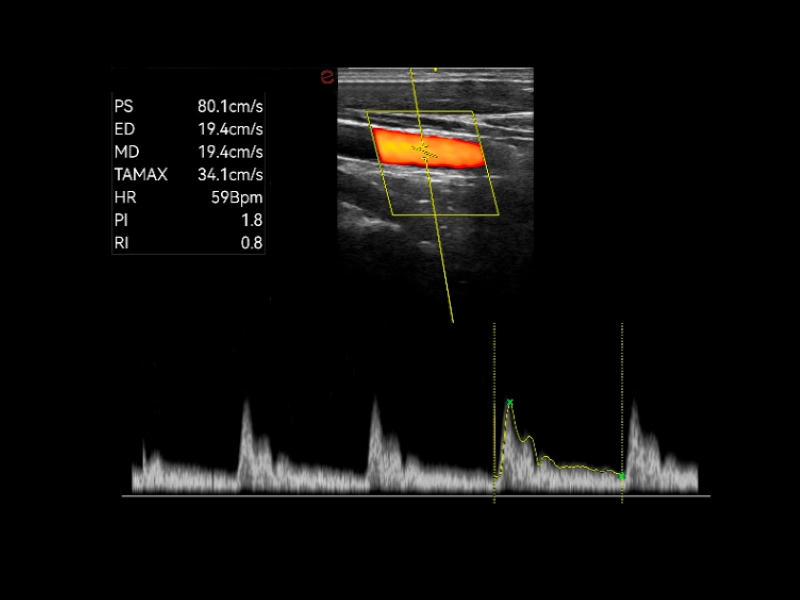

Q7 - Carotid

Q7 - Carotid

Q7 - Doppler

Q7 - Doppler